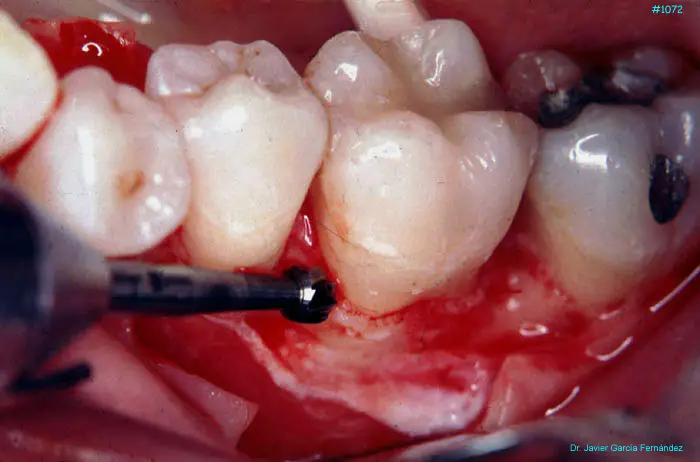

Atlas of Surgical Techniques in Periodontics. Chapter III. Atlas de Técnicas Quirúrgicas en Periodoncia